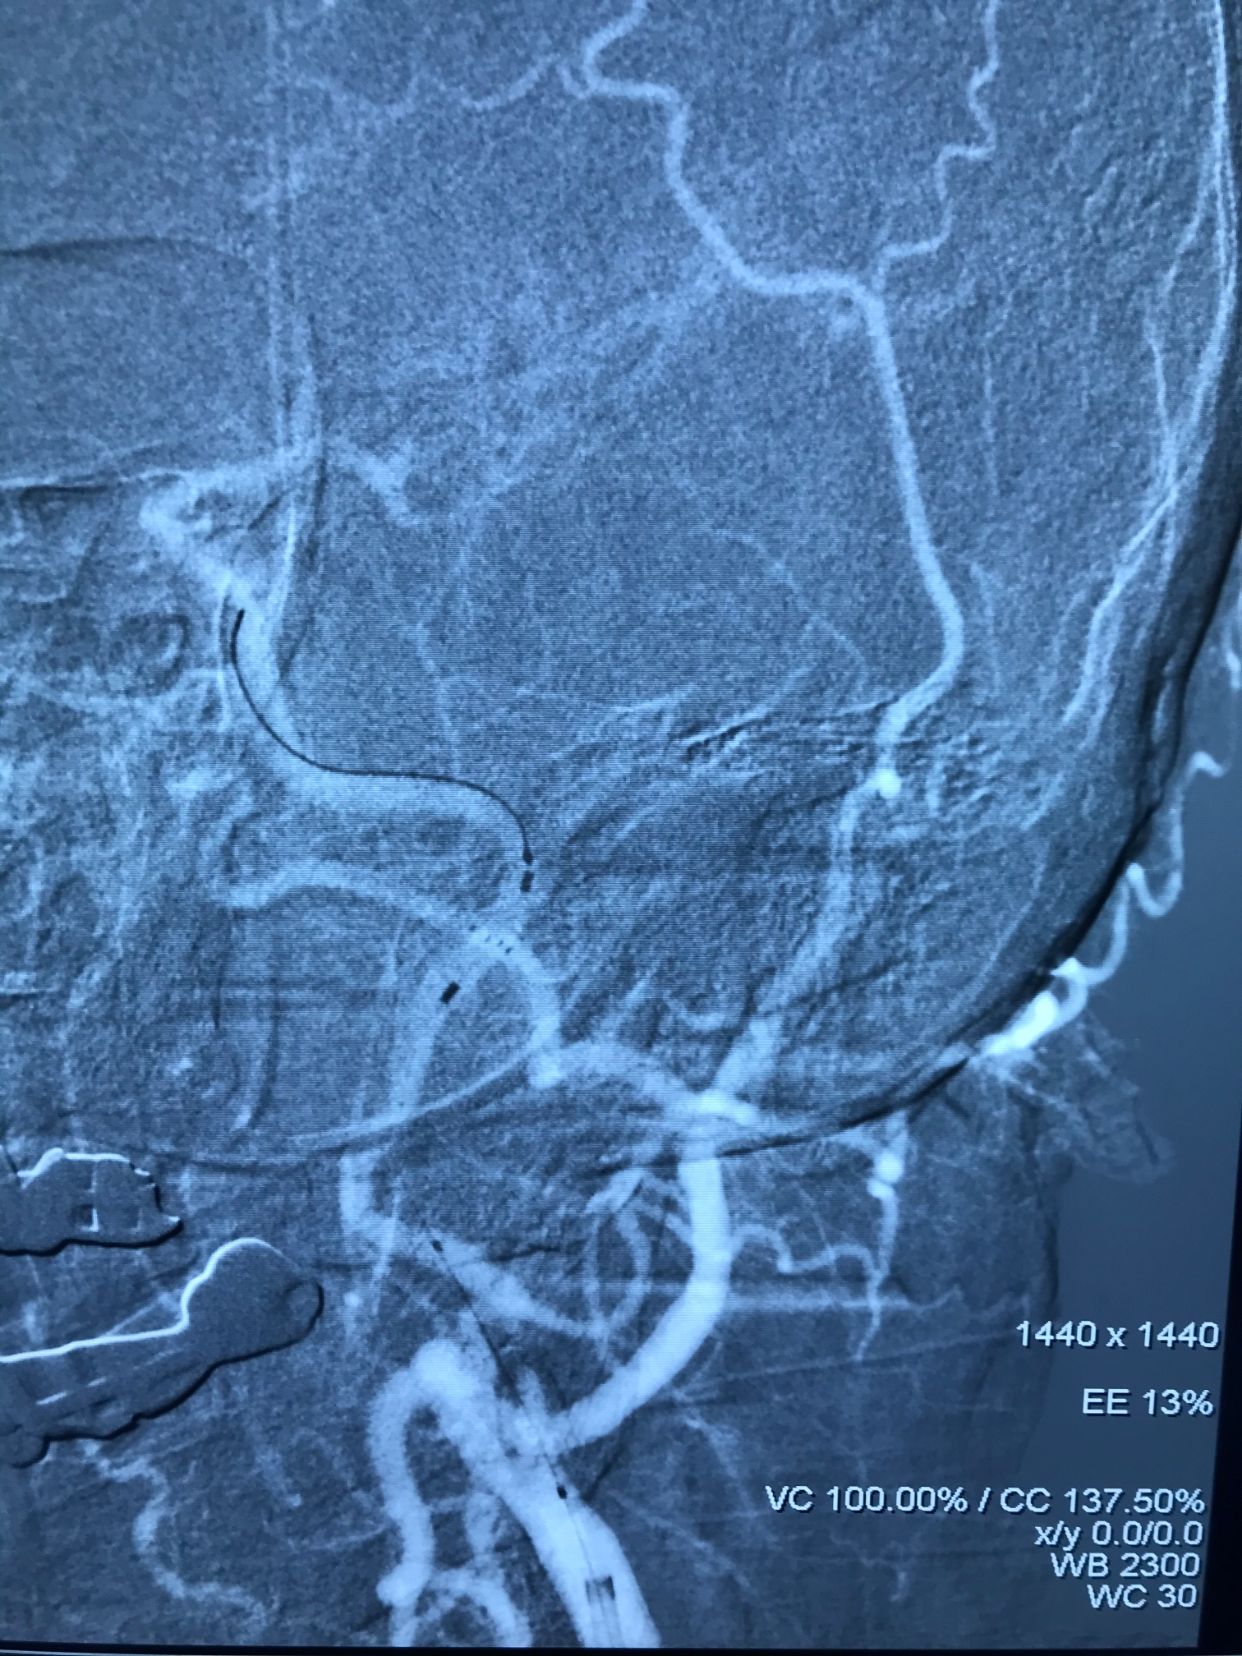

MRA示左侧颈内动脉开口重度狭窄!

左侧颈内动脉供血区显影差!